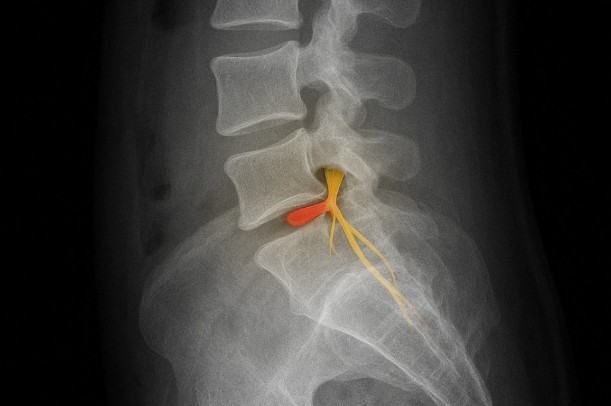

一方、特異的腰痛は、検査によって原因を特定できる腰痛とされ、椎間板ヘルニアや脊柱管狭窄、圧迫骨折など、構造的な変化が痛みにつながるケースが含まれます。参考記事でも、背骨や椎間板などの組織が関係する場合は、しびれや感覚の低下、歩行のしづらさなどが現れることがあると説明されています(引用元:https://www.mediaid-online.jp/clinic_notes/information/1920/ )。

腰痛 原因の中でも、背骨そのものに変化が起きて痛みが出るタイプは「特異的腰痛」に分類されると言われています。背骨は椎骨と椎間板が積み重なって構成され、その周囲には神経や靭帯が張り巡らされています。このどこかに負担が集中すると、腰まわりに鋭い痛みや動かしづらさが出ることがあると説明されています。参考記事でも、骨や椎間板の状態によって痛みの出方が変わるとされており、動くと痛む、しびれを伴うなど、特徴的な症状が現れる場合があるとまとめられています(引用元:https://www.mediaid-online.jp/clinic_notes/information/1920/ )。

椎間板ヘルニア ― 神経を圧迫したときに起こりやすい症状

椎間板ヘルニアは、背骨の間にあるクッションのような組織が飛び出し、神経に触れることで痛みやしびれが出ると説明されています。腰痛 原因の中でもよく知られ、前かがみ姿勢で悪化しやすかったり、脚にしびれが広がったりするケースもあると言われています。参考記事では、椎間板の変性は加齢や姿勢のクセ、重い物を持つ動作などがきっかけになる場合があると紹介されていました。痛みの強さに波があり、朝と夕方で感じ方が変わる人もいると説明されています(引用元:https://www.mediaid-online.jp/clinic_notes/information/1920/ )。

脊柱管狭窄 ― 歩くとつらくなる特徴的な腰痛

脊柱管狭窄は、神経の通り道が狭くなることで腰から脚にかけて症状が出やすいとされています。特徴として、しばらく歩くと痛みやしびれが出て、座ったり前屈したりすると楽になる傾向があると言われています。加齢による骨の変化や靭帯の肥厚が背景にあることも多く、腰痛 原因の中でも中高年層が悩みやすいと説明されています。参考記事でも、脊柱管狭窄は神経症状の有無が判断のヒントになるとまとめられています(引用元:https://www.mediaid-online.jp/clinic_notes/information/1920/ )。